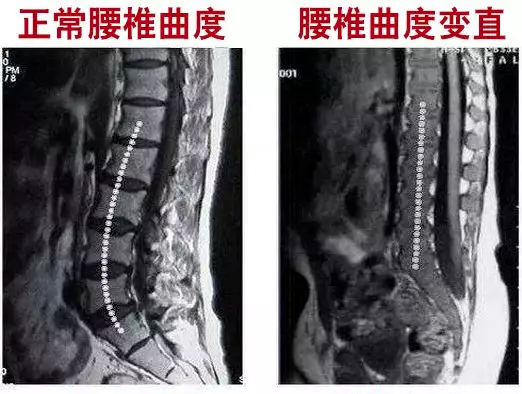

大部分腰部不适,根源上都来自于「腰椎变形」!

所以想要缓解腰疼,让腰直起来,必须让变形的腰椎回到正常!

这款护腰就根据腰椎曲度生理特征,采用仿生脊椎支撑系统

人体腰椎有26°的生理曲线,而4块钢板也有26°的记忆弧度,

在腰椎两侧,一左一右各2块贴合撑托,减轻腰椎压力。